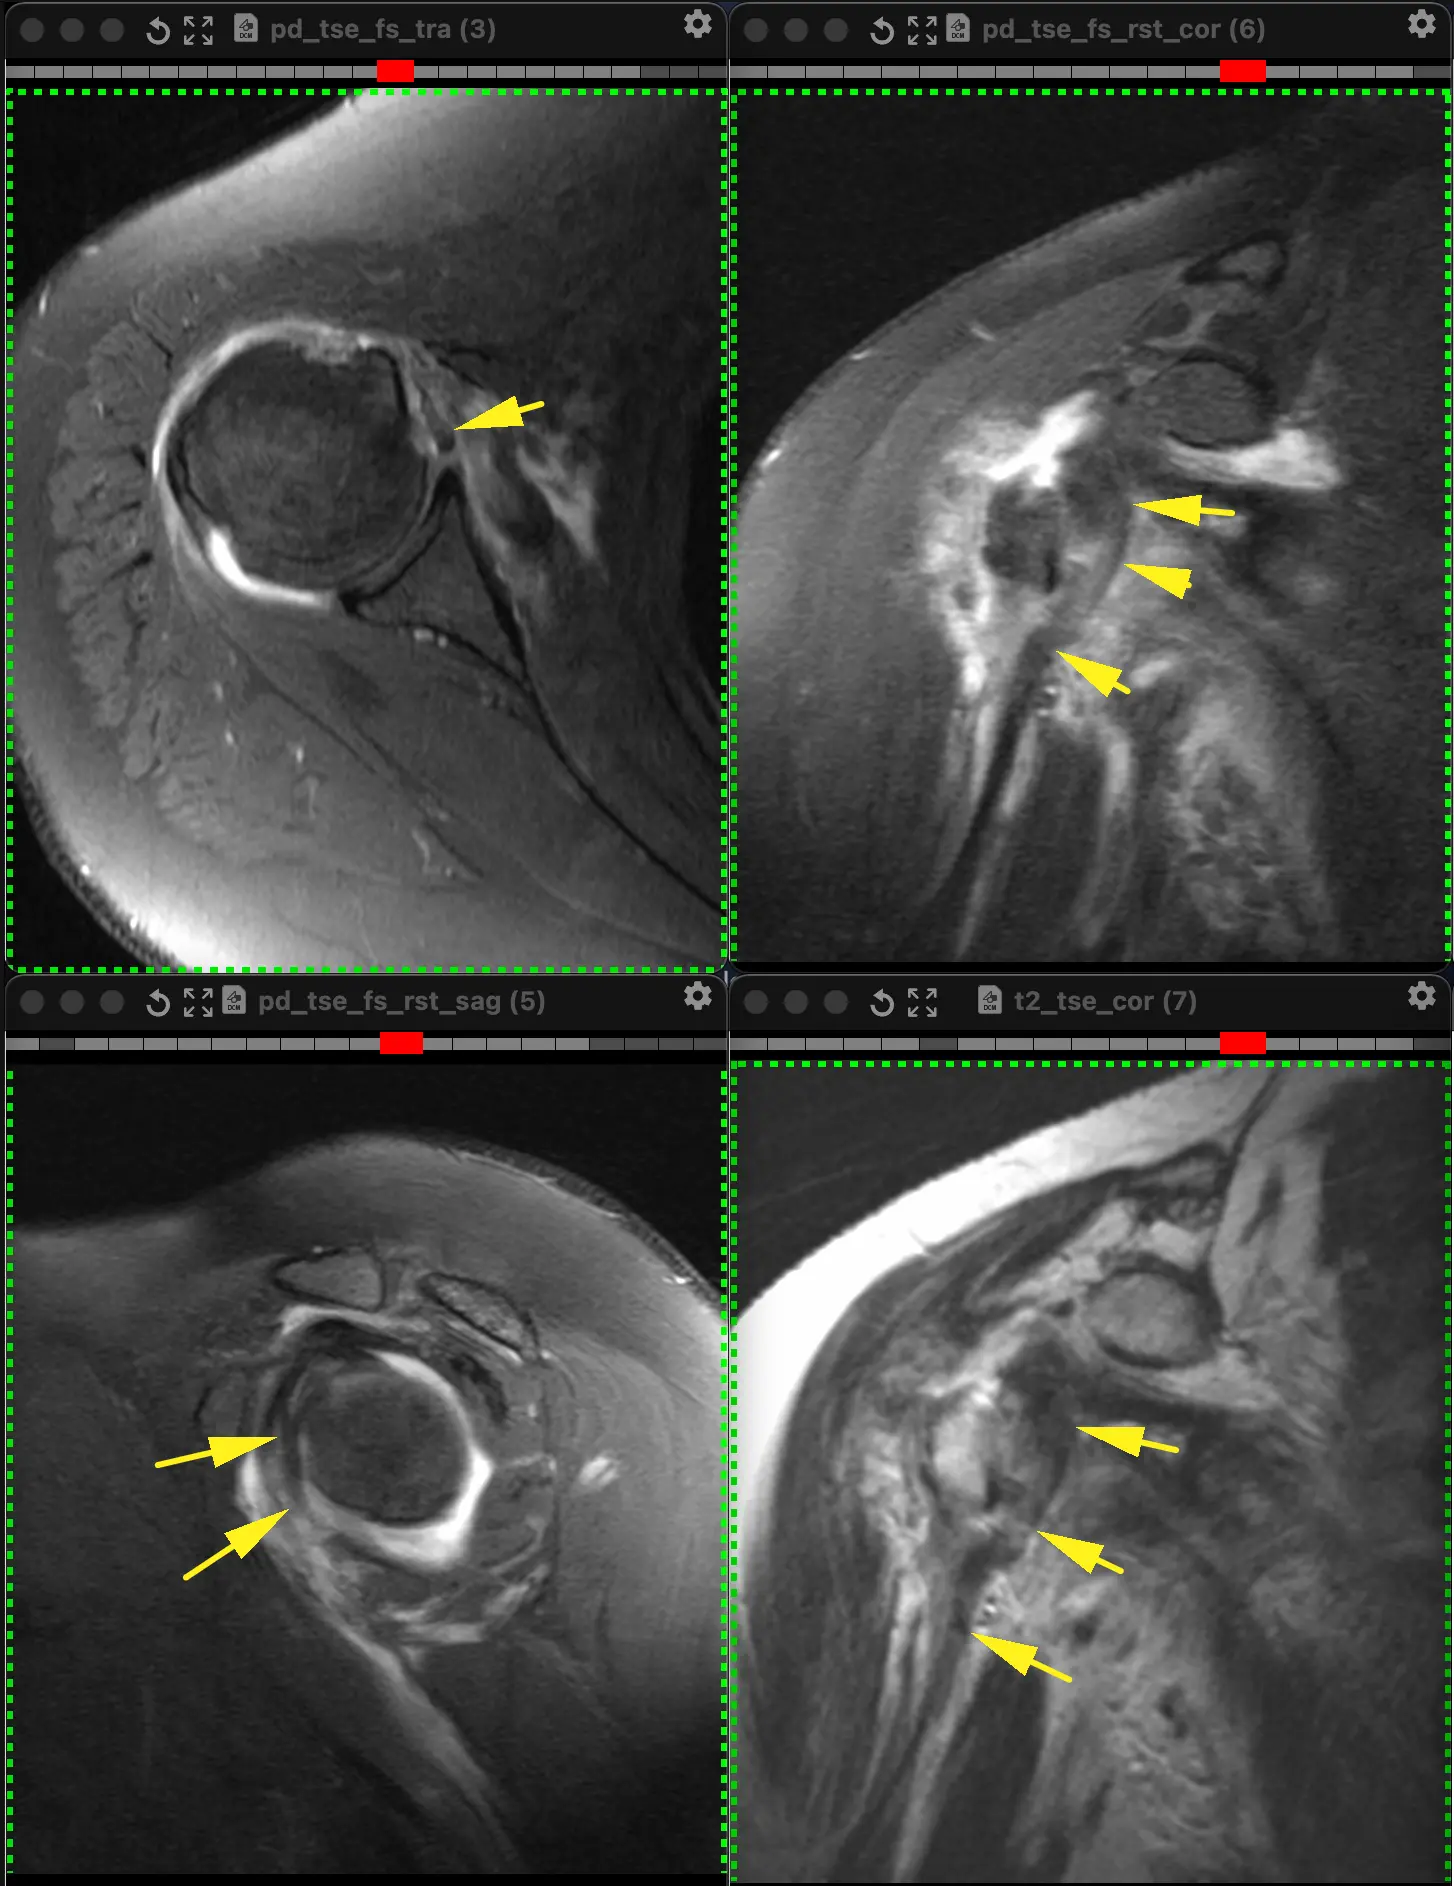

Вот такие плечики у пациента 29 лет! Во время эпидемии COVIDa-19 перенёс тяжёлую форму, лечили, в том числе, высокими дозами кортикостероидов, так что остеонекроз, который мы имеем возможность видеть в головках плечевых костей, по всей видимости, развился, как осложнение этого вида терапии. Хотя, при этой инфекции возникает ещё и гиперкоагуляция, которая и сама по себе является фактором риска развития некроза костей. В литературе такие случаи описаны и известны, есть описания развития остеонекроза даже четырёх костей одновременно (головок бедренных и плечевых костей), причём, развился он аж через полгода после окончания терапии. В нашем случае справа некроз привед к фрагментации головки плеча. Понятное дело, что функции плечевых суставов нарушены, в том числе, за счёт развития грубого вторичного артроза. Видимо, тотальная артропластика потребуется...

А вот вдогонку ещё костное повреждение Банкарта, парень 20 лет. Последствия переднего вывиха плеча.

Из-за отрыва сухожилия подлопаточной мышцы вывихнулось медиально сухожилие длинной головки бицепса. Сухожилие подлопаточной мышцы является одновременно удерживателем длинной головки бицепса в межбугорковой борозде, вплетаясь в малый бугорок плеча и как бы продолжаясь в поперечную связку (связку Броди), которую некоторые считают не истинной связкой, а частью сухожилия надостной мышцы.